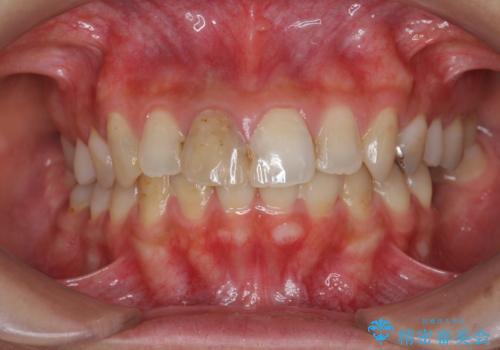

- 前歯の見た目、変色の改善を希望され来院されました。

ジルコニアクラウンによる審美性の改善を計画します。

神経の治療をした歯について

神経をとる治療を行った歯は、時間が経過すると術前のように変色し見た目を大きく損ないます。

このような場合金属を使わないジルコニアクラウンを用いた治療を行うことで天然の歯のように審美性を改善することが可能になります。